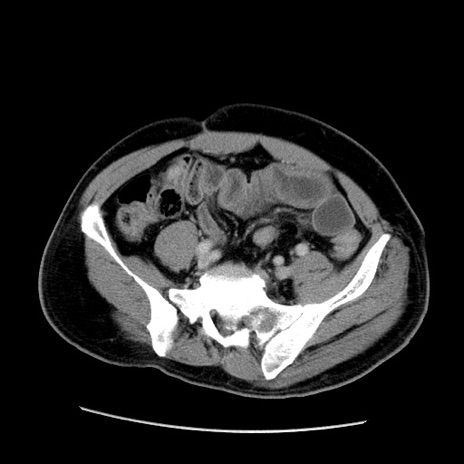

症例22(横断像)

【症例】50歳代男性

【主訴】腹痛

【現病歴】AVMからの被殻出血のため回復期リハ病棟入院中。 本日午後3時頃急に下腹部痛が出現した。

【既往歴】AVM、被殻出血、虫垂炎、高血圧

【身体所見】意識晴明、左半身不全麻痺、会話の理解は良好、36.5°C、腹部:膨隆、全体に板状硬、下腹部正中に圧痛点あり、反跳痛-、筋性防御不明、右下腹部にope scar

【データ】WBC 9400、CRP 0.06